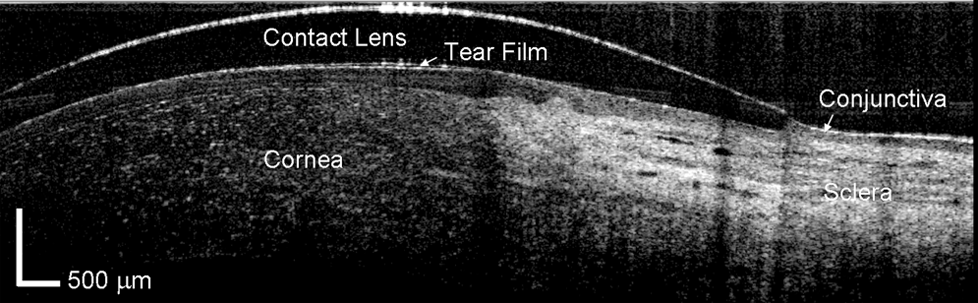

Lentes de contacto esclerales: La gran alternativa.